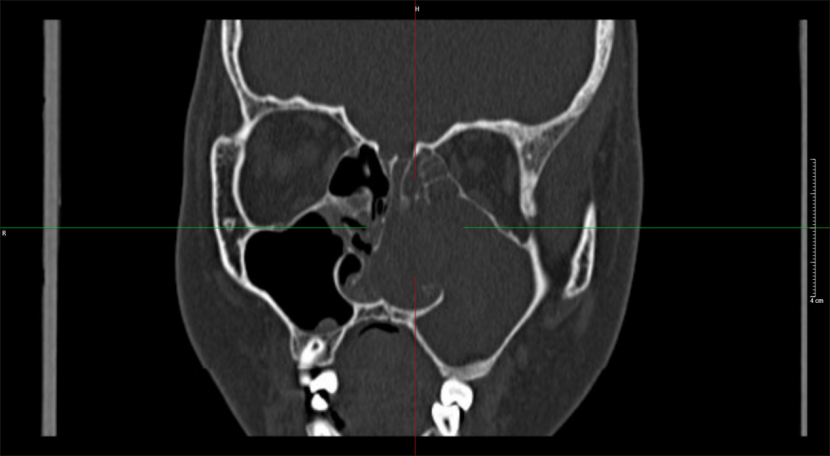

为求进一步规范治疗,家长带她来到济南南郊医院。耳鼻喉科杨钦龙主任接诊后,经详细专科检查,发现小患者左侧鼻腔存在单侧进行性鼻塞、流涕、反复出血情况,右侧鼻腔被出血性息肉完全占据,已致鼻中隔偏曲,鼻窦骨质结构受累、形态改变,具备手术干预指征。

术中,杨主任凭借精湛操作技术与丰富临床经验,精准切除患者鼻腔内肿物,同时对慢性鼻窦炎、肥大性鼻炎进行有效矫治。术后病理结果为出血坏死性息肉,明确病因。目前,患者恢复态势良好,鼻塞、流涕等症状明显缓解,嗅觉逐步恢复,有望摆脱长期鼻腔疾病困扰,回归健康生活。